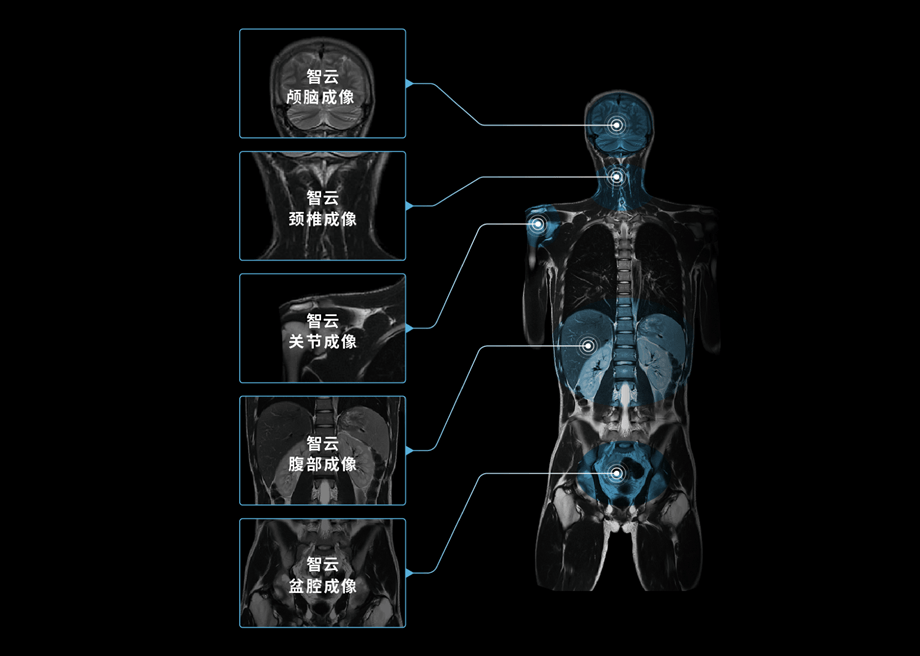

智云平台

智云磁体

自主研发的匀场技术,优异的磁场均匀度。

智云梯度

智能涡流补偿技术,高梯度性能。